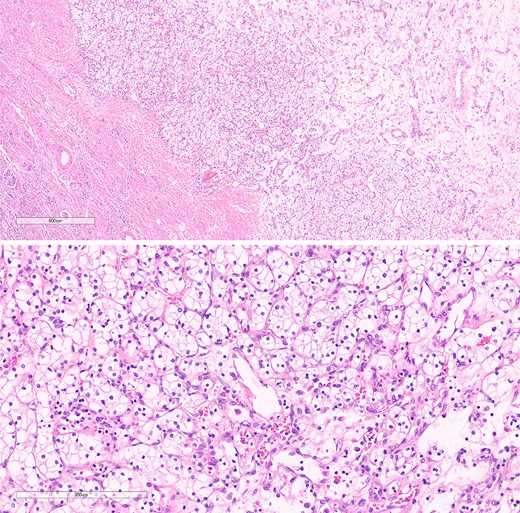

The pathological analysis of the kidney mass was revealed to be ccRCC, measuring 6.0 × 4.7 × 3.5 cm with a histologic grade of G2. The tumor extension was limited to the lower pole of the right kidney. All margins were negative for invasive carcinoma, and 10% tumor necrosis was identified. In this case, the TNM staging of RCC was classified as T1bN0M0 [8]. The sigmoid colon mass was revealed to be grade G2—moderately differentiated, adenocarcinoma measuring 5 cm at the maximal diameter (Fig. 7). The cancer has shown invasion through the muscularis propria into the pericolic fatty tissue. Fortunately, the proximal resection, distal resection, and mesenteric resection margins showed no involvement by the invasive carcinoma. In addition, all of the 15 biopsied lymph nodes showed no metastasis. In this case, the sigmoid colon cancer was staged as T2N0M0 [9].

Histological section of sigmoid colon cancer showing atypical glandular structures consistent with adenocarcinoma.